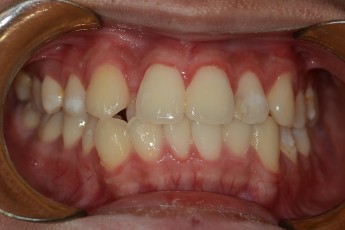

Before & After

- 돌출입교정

Before

After